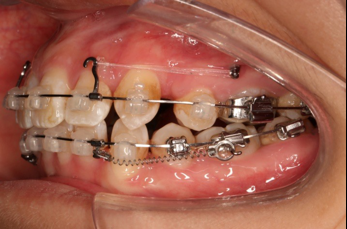

6.第9个月:2017.07.25 ◆ 上前牙加颈部弹力线

2017.07.25

2017.07.25  上前牙加颈部弹力线

2017.10.07

2017.10.07  继续关间隙,下颌使用水平关间隙